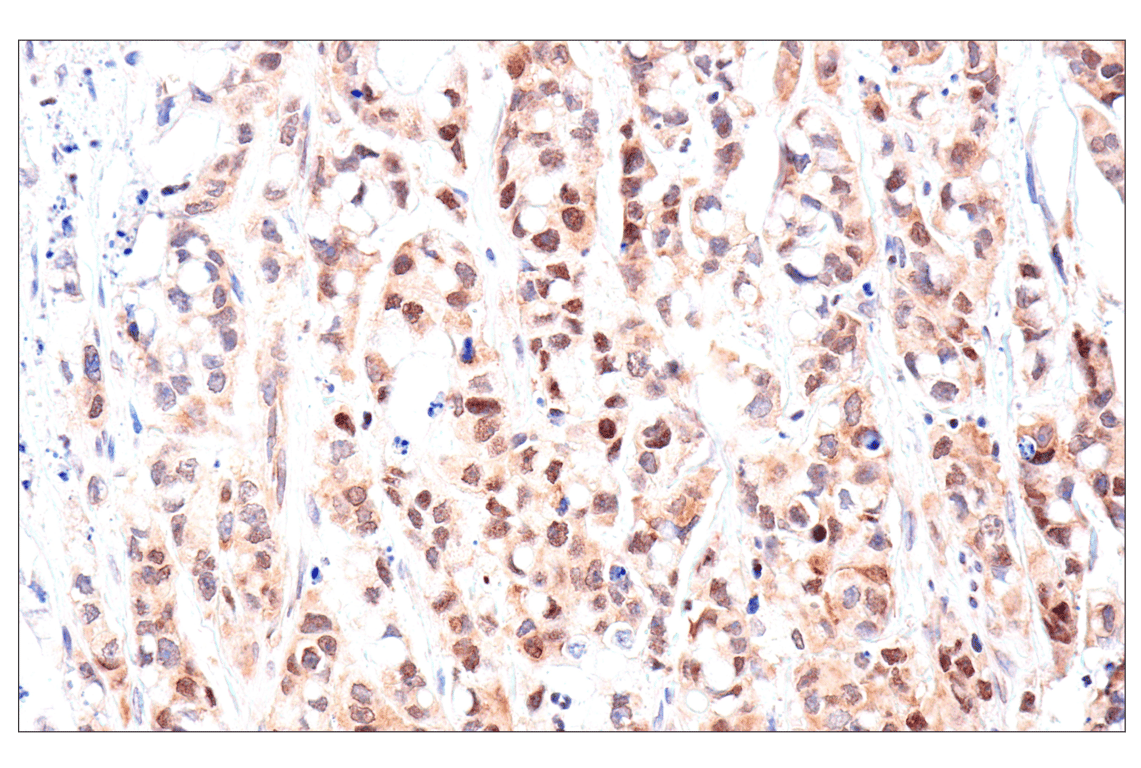

Immunohistochemical analysis of paraffin-embedded human oropharyngeal squamous cell carcinoma using ADAR1 p150 Isoform (E6U1U) Rabbit mAb.

Immunohistochemistry Image 2: ADAR1 p150 Isoform (E6U1U) Rabbit Monoclonal Antibody